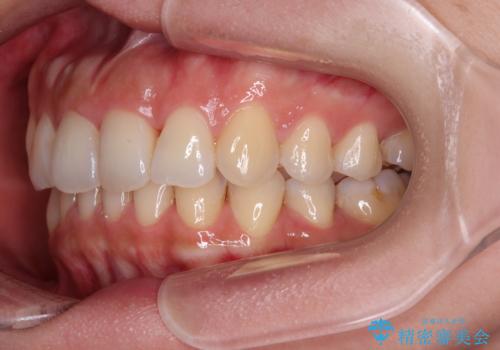

- 捻れた前歯が飛び出しており、口が閉じにくいとのことで来院された患者様です。

出っ歯というわけではないものの、前歯の捻転により口唇が押し出されている状態でした。

親知らずを抜去し、歯列全体を後方に移動させつつ、IPR(歯と歯の間を削る)でスペースを獲得し、インビザラインを用いて叢生を解消しながら前歯の突出を改善することとしました。

骨格的に上下正中がずれていたため、奥歯がしっかりと噛み合うか心配でしたが、ずれているなりに、しっかりとした咬み合わせとなりました。